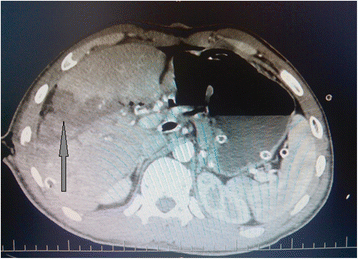

At post-operative period, a computed tomography (CT) scan of the abdomen was performed. At CT analyses showed the liver to demonstrate zones with ischemic lesions (Fig. 3). Considering liver CT data, a liver resection of the affected segment was planned to prevent further necrosis and abscess formation according to DC tactic. However, on the 16th day after the injury, intra-abdominal bleeding was diagnosed and urgent laparotomy was performed. At revision, erosion of the right hepatic artery was detected (Fig. 4a) as a result of the chronic inflammation of the artery wall and continuous contact to the bile. Erosive defect was sutured and stable hemostasis was achieved (Fig. 4b). At revision of sutured areas of the liver, we found it to be covered with fibrin, partial failure of sutures and bile leakage were observed. Furthermore, tissue softening and color changes of liver S5–6 parenchyma were detected, indicating ischemic failure (Fig. 5a). In order to stop bile leakage and to prevent liver failure, a decision was made to perform anatomic resection of the liver S5–6 (Fig. 5b). Due to the critical status of the patient and considering DC approach, we postponed the surgery for stabilization of hemodynamics by resuscitation and transfusion of one-group packed red blood cells. At the ninth day after the liver resection, the patient was transferred to the surgery ward from ICU.